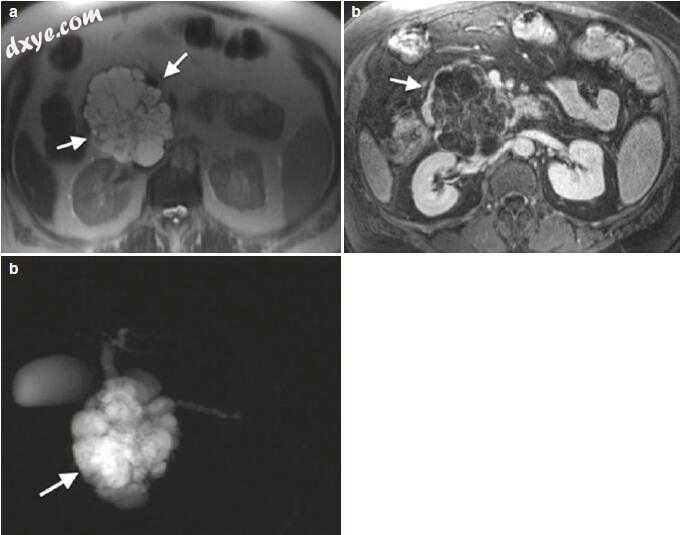

通常,这些肿瘤是罕见的并且占所有胰腺肿瘤的约5-7%,最常见的亚型是胰岛素瘤,胰高血糖素瘤和非激素活性肿瘤。各种PanNEN的成像特征通常非常相似,使得免疫组织化学染色成为一个关键问题,特别是当特定激素释放不是主要的临床症状时(图14.3)。

3.jpg

图14.3(a-d)小神经内分泌肿瘤。 (a)具有脂肪饱和度的轴向T1加权梯度回波图像(TR / TE 180 / 4.66ms)显示神经内分泌肿瘤与邻近的胰腺实质相比呈现低信号(箭头)。 (b)轴向T2加权涡轮自旋回波图像(TR / TE 4500/102)显示一个小的神经内分泌肿瘤,与邻近的薄壁组织相比呈现高信号(箭头)。 (c)在Gd-螯合物给药后的动态研究的胰腺期,轴向脂肪饱和体积T1加权梯度回波图像(TR / TE 4.86 / 1.87ms),与邻近胰腺实质相比,神经内分泌肿瘤出现高信号。 (箭头)。 (d)在轴向弥散加权像(b = 1000)上,神经内分泌肿瘤表现出有限的扩散(箭头)